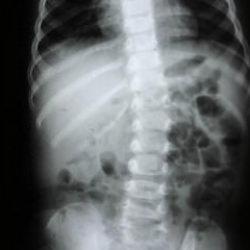

Omurga sağlığı için nelere dikkat edilmeli? Uzman isim açıkladı